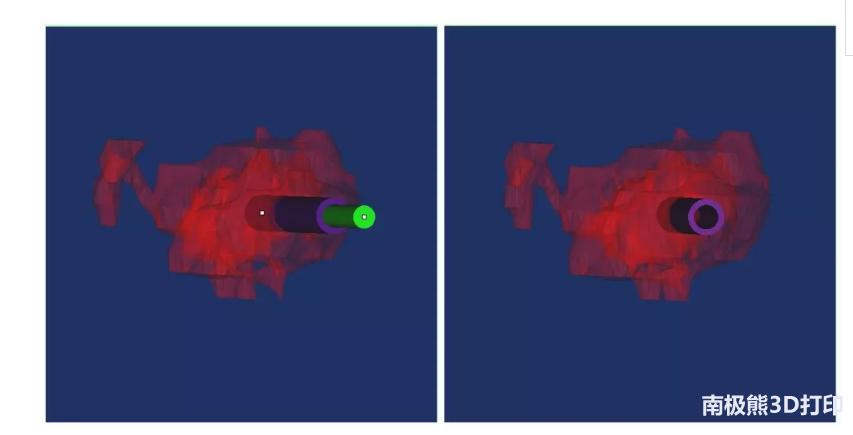

圆柱体的三维重建效果图

穿刺通道的三维重建效果图